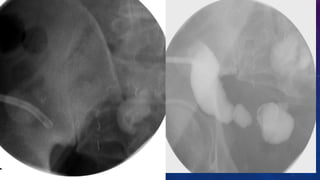

SEVERELY DILATED URINARY BLADDER WITH

DIVERTICULAE AND CALCULI